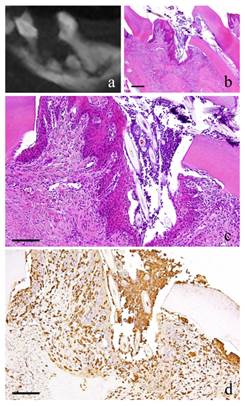

Figure 3

3-month-specimen. a: m_CT image; b: Histopathological view of the same part of a, Scale bar=200μm; c: Enlarged view of b, Scale bar=100μm; d: IHC for GFP, Scale bar=100μm.

Int J Med Sci Image

At 3 months, the nucleus of fibroblasts in the granulation tissue became flat. Proliferation of collagen fibers was also evident. Likewise, the stratified squamous epithelial lining became thicker. Capillaries in the granulation tissue also increased at its peak (Fig. 3-b, c).

At 2 weeks, long and spindle in shape cells with spindle shape nucleus as well as vascular endothelial cells were positive to GFP. In addition, multinucleated giant cells in the area of alveolar bone resorption were also positive to GFP (Fig. 1-d).